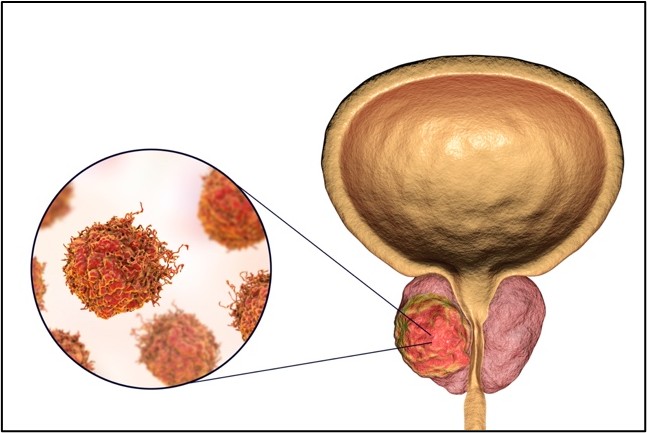

Prostat, vücudumuzdaki ürogenital sistemin bir parçası olan organdır (Şekil 1). Mesanenin altında bulunur ve içerisinden idrar yolu geçer. Prostatın vücuttaki fonksiyonu; içinde spermlerin bulunduğu meni (semen)’nin hacmine katkıda bulunmaktır. Bunun yanında meninin içerisine prostat spesifik antijen (PSA) denen bir enzim katar. Bu enzim meninin kıvamının incelmesi yoluyla spermlerin daha kolay hareket etmesine olanak sağlar.

Şekil 1: Prostat ve prostat kanseri